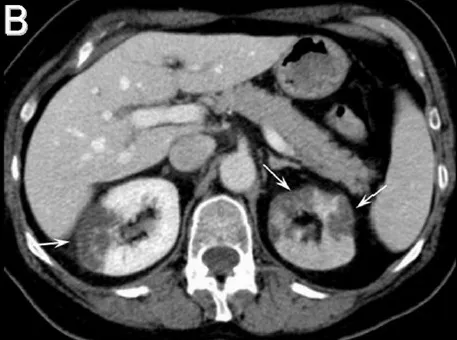

Uma causa incomum de hematúria glomerular intermitente!

Hematúria pós infecção, caso clínicos para auxiliar no entendimento de causas glomerulares comuns e raras...